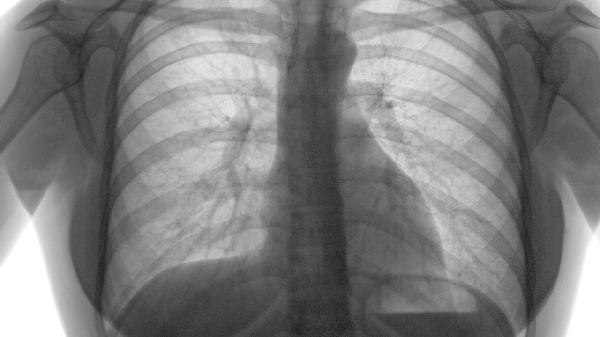

肺氣虛可能由先天稟賦不足、長(zhǎng)期勞累、久病耗傷、環(huán)境因素、情志失調(diào)等原因引起。肺氣虛通常表現(xiàn)為氣短乏力、易感冒、自汗、語(yǔ)音低微等癥狀。

慢性支氣管炎、肺結(jié)核等呼吸系統(tǒng)疾病遷延不愈,會(huì)持續(xù)損耗肺氣。這類患者常伴有咳嗽痰多、胸悶等癥狀。需積極治療原發(fā)病,可遵醫(yī)囑使用補(bǔ)肺湯加減等中藥方劑,或玉屏風(fēng)顆粒、生脈飲口服液等中成藥。